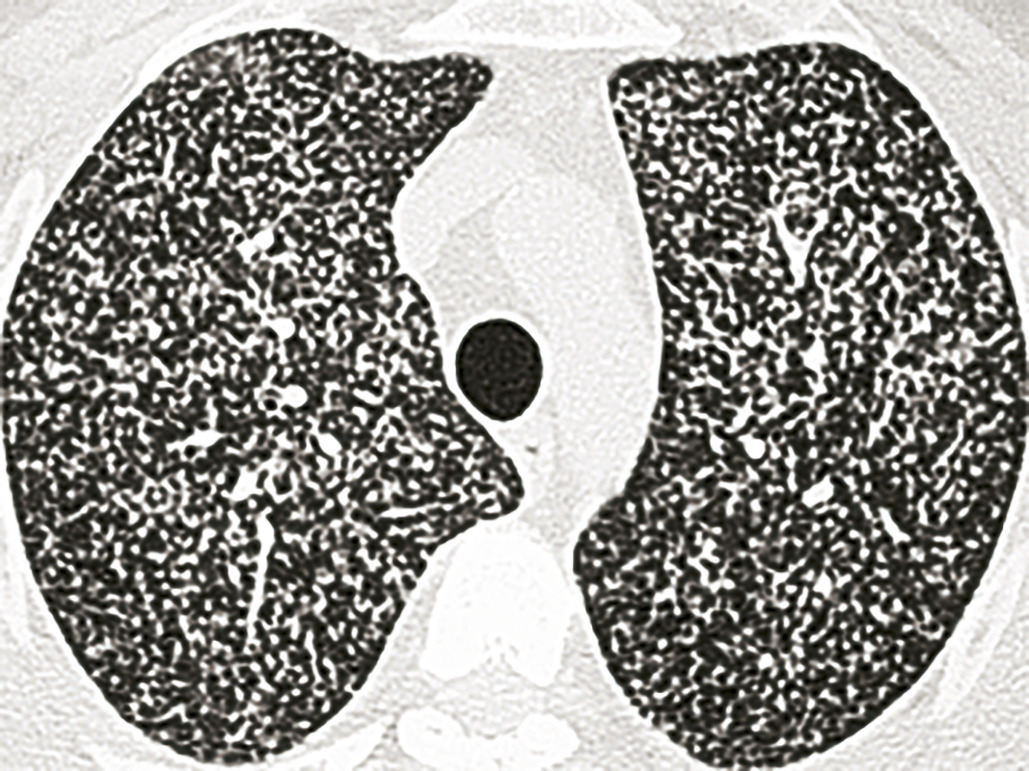

Imagerie (fig.1-4)

L’imagerie thoracique (radiographie, tomodensitométrie plus précise) révèle des opacités et modifications morphologiques de plusieurs types ± associées : atteintes bronchiolaires, bronchocèles, nodules acinaires, masses ± excavées, formes pneumoniques, rétractions lobaires, adénopathies médiastinales, pleurésies, miliaires.